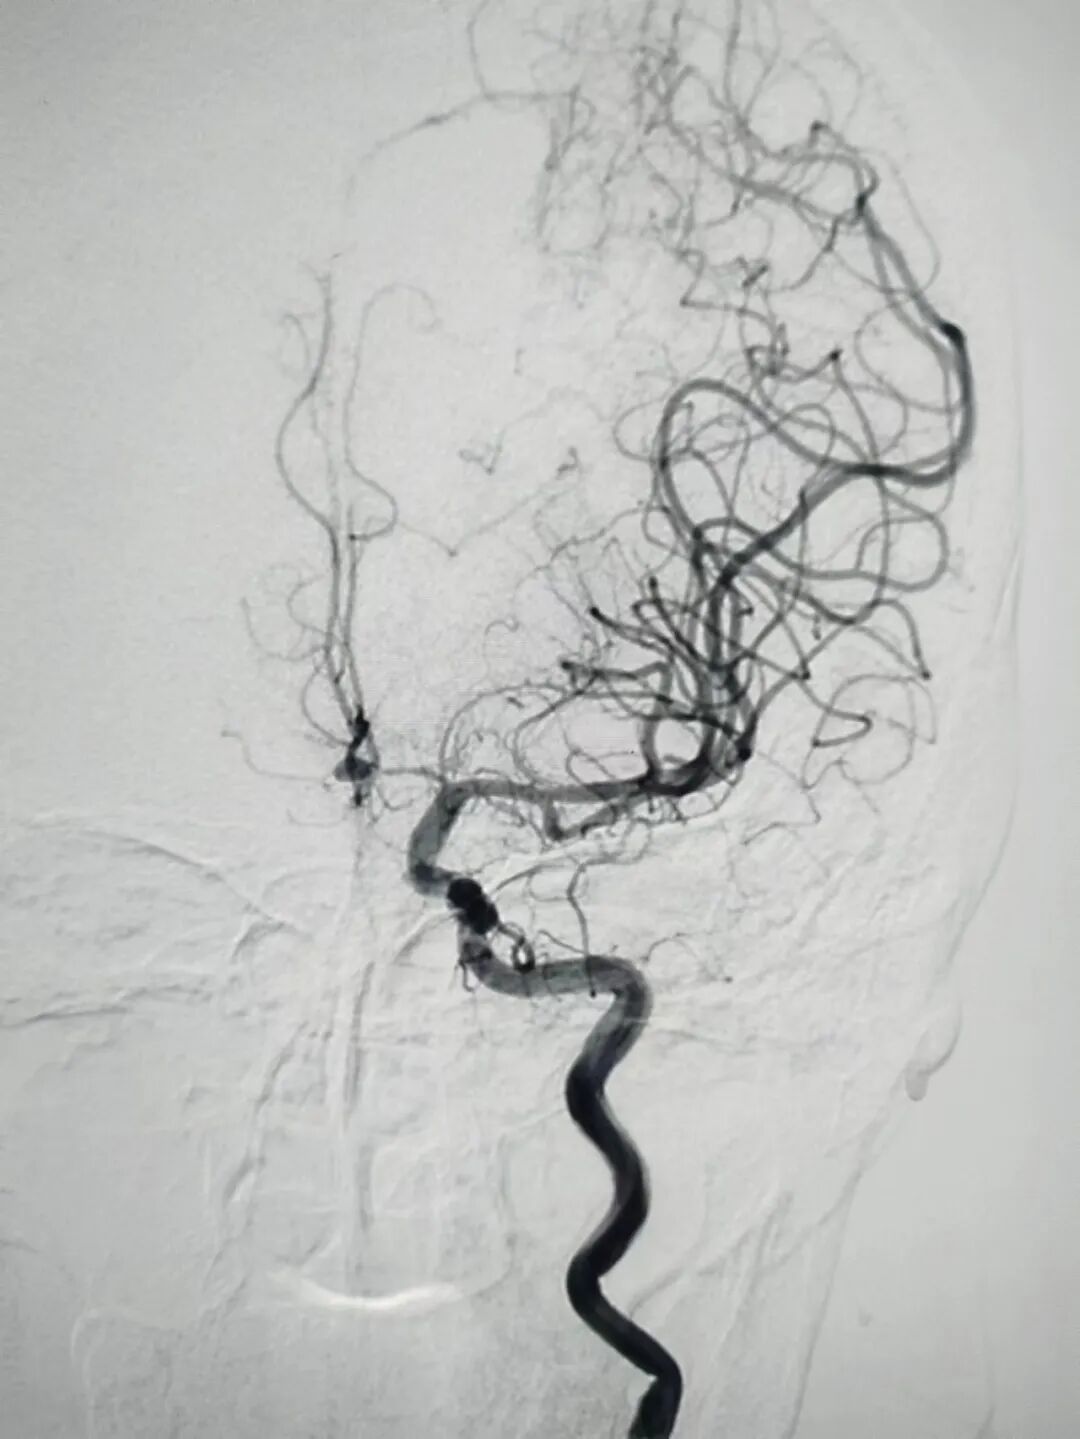

近日,我院神經(jīng)外科吳偉濤主任領(lǐng)導(dǎo)的團(tuán)隊(duì)成功為一名54歲女性患者實(shí)施了前交通動(dòng)脈瘤開(kāi)顱動(dòng)脈瘤夾閉手術(shù),經(jīng)過(guò)術(shù)前仔細(xì)評(píng)估,術(shù)中精準(zhǔn)操作,術(shù)后細(xì)心護(hù)理,最終患者取得滿意療效。

顱內(nèi)動(dòng)脈瘤開(kāi)顱夾閉術(shù)是臨床中常用的治療動(dòng)脈瘤的手術(shù)方法,其目的在于阻斷動(dòng)脈瘤的血液供應(yīng),避免發(fā)生再出血,保持載瘤及供血?jiǎng)用}繼續(xù)通暢,維持腦組織正常血運(yùn)。相比介入手術(shù),該手術(shù)方法治療費(fèi)用低,術(shù)后不易復(fù)發(fā),目前洛陽(yáng)伊洛醫(yī)院神經(jīng)外科兩種手術(shù)方式均已開(kāi)展,僅2月份就開(kāi)展了動(dòng)脈瘤夾閉術(shù)3例,均取得良好效果。